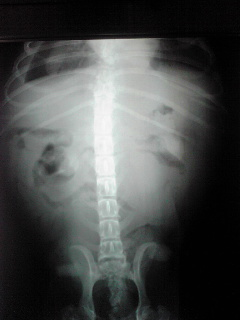

状態、非常に悪く、元気・食欲なく、痩せているにもかかわらず、お腹は膨れて、呼吸もままならず、X線では胸水が溜まり、その性で心臓もよく写っていない状況でした。